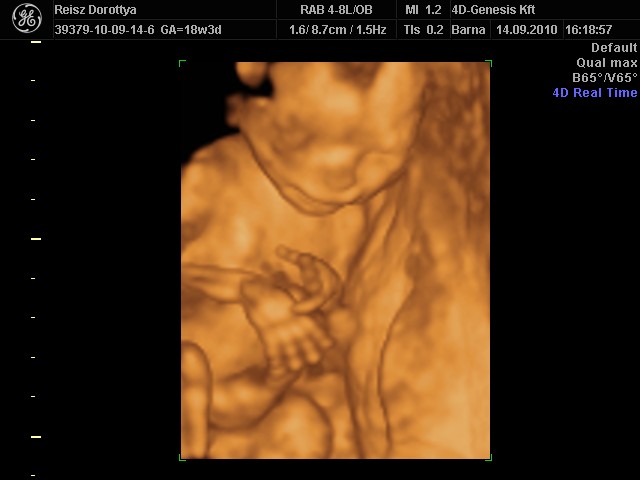

Nem tudom mikor lesz, de február közepére várjuk az ifjú fikagépet és tehát vagy nagyon az utsó időben lesz amikor asszonka sztem nem kívánja majd a hosszú út és hangos zene no meg ifjú férjecskéje utáni aggódás viszontagságait, ha meg utána akkor meg túl pici lesz a kölök egy ilyen kiruccanáshoz. Hadd nyugodjanak a kedélyek, és legyen idő gyűjteni a még színvonalasabb bálra, hogy többet szó ne érje a ház elejét vagy zenéjét. :-) Húúú de bátor vagyok...vagy vak.. |